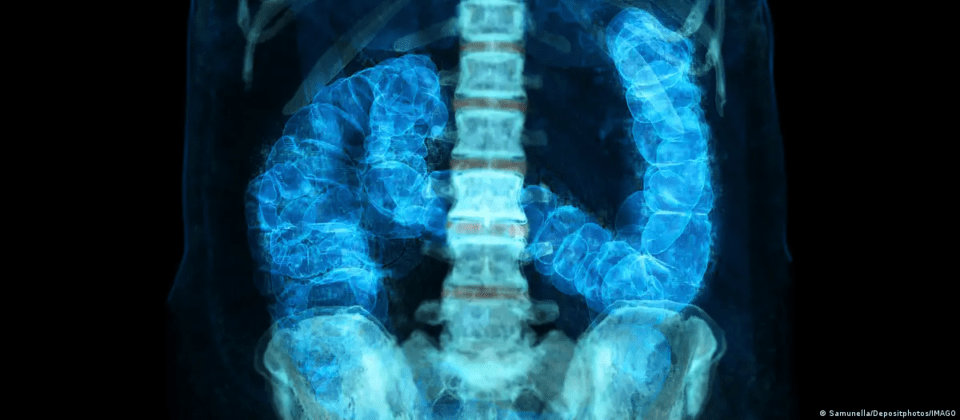

Aumenta el cáncer colorrectal en jóvenes: los factores que elevan el riesgo

Mundo, 17 de feb 2026 (ATB Digital).- El cáncer colorrectal no es solo una amenaza para los adultos mayores, sino cada vez más para hombres y mujeres jóvenes. Ahora es el principal tipo de cáncer mortal entre los estadounidenses menores de 50 años.

Además, dónde ocurre el cáncer a lo largo del colon en forma de signo de interrogación –comienza en un lado del abdomen y se curva hacia el otro antes de terminar con el recto– influye en qué tan agresivo es y cómo se trata. Marshall dijo que hay una marcada diferencia en dónde tienden a aparecer los tumores de las personas más jóvenes y mayores, otra pista que se está explorando.